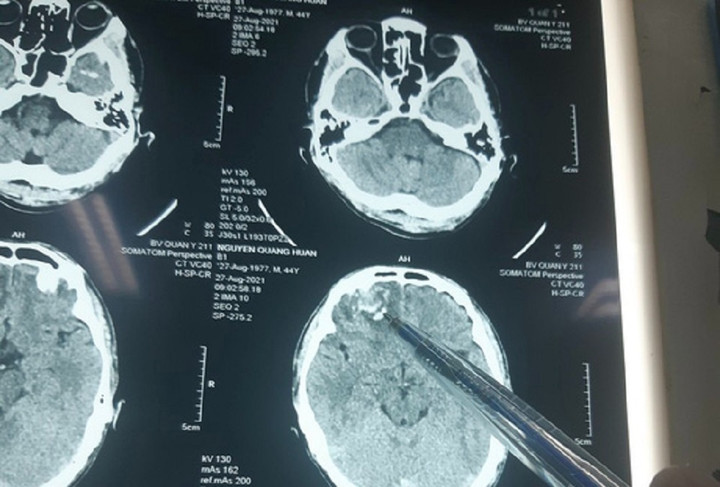

Kết quả chụp của bác sĩ cho thấy ông Huấn bị chấn thương sọ não, tổn hại 35% sức khỏe.

Liên quan vụ việc, trước đó, bà Hoài có đơn gửi Công an huyện Chư Sê trình báo việc tối 23/8/2021, khi đang chở ốc từ xã Ayun lên thị trấn Chư Sê, chồng bà là ông Nguyễn Quang Huấn bị nhóm người của HTX Sản xuất nông nghiệp Ayun Thịnh vây đánh chấn thương sọ não, tổn hại 35% sức khỏe.